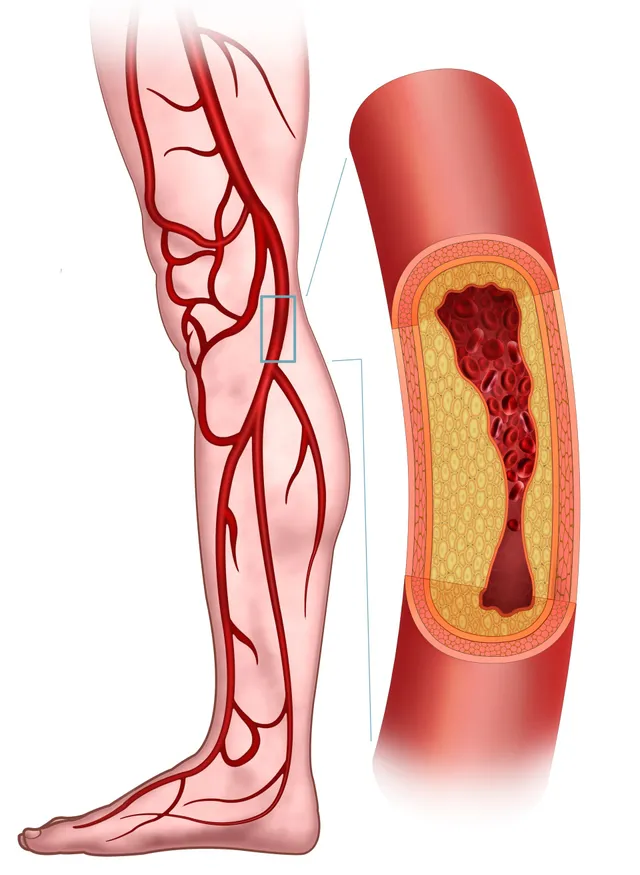

Peripheral Arterial Disease